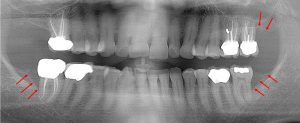

This 48 year old patient had all four 3rd molars extracted in his late 20’s. All four sites healed poorly and chronically infected bony defects remained. The upper right 2nd molar was extracted two years ago as a result of this chronic infection. The upper left 2nd molar must now be extracted because of a chronic periodontal infection moving around that tooth. Both lower molars are chronically infected and have a poor prognosis.

This 52 year old patient had the lower right 3rd molar extracted 6 years earlier due to a chronic infection. The boney defect (arrows) posterior to the 2nd molar (circled) is a site with a chronic gum infection present. Repeated cleaning is necessary to prevent further bone loss around the 2nd molar. Note the other two 3rd molars laying in the bone.